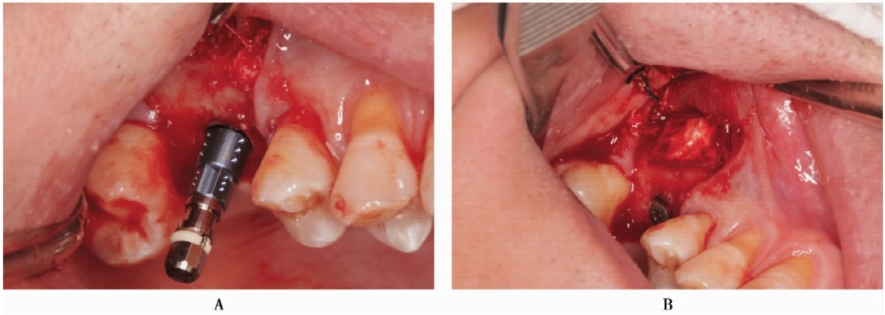

超声骨刀侧壁开窗,剥离上颌窦黏膜(图13A)。但在剥离的过程中,由于开窗中央骨块锐利的边缘,侧壁上颌窦黏膜发生穿孔(图13B)。采用胶原膜封闭穿孔后,植入Bioss®骨粉,采用延期种植。

图13 侧壁开窗A.超声骨刀开窗;B.分离窦黏膜,但出现小的穿孔